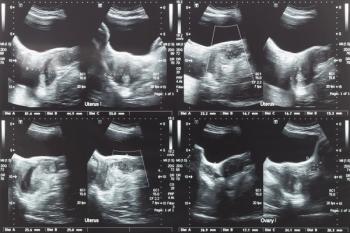

A study has once again validated ultrasound-guided high-intensity focused ultrasound (USgHIFU) as an effective technique to devascularize uterine fibroids.